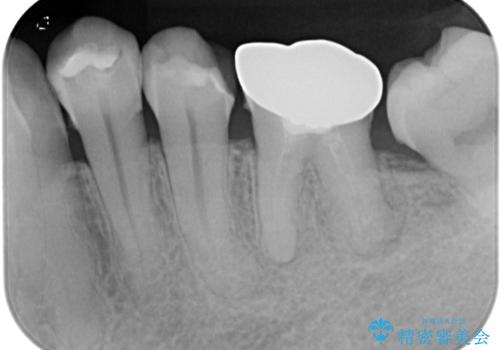

下顎大臼歯の再根管治療とオールセラミッククラウンによる補綴治療

- 10年以上前に治療した銀歯をやり替え希望で来院された患者様です。

噛んだ時に少し違和感があり、レントゲン上で根尖病変が確認できるため再根管治療を行いました。

根管治療後は、ファイバーコアによる土台と、オールセラミッククラウンによる補綴治療を行いました。